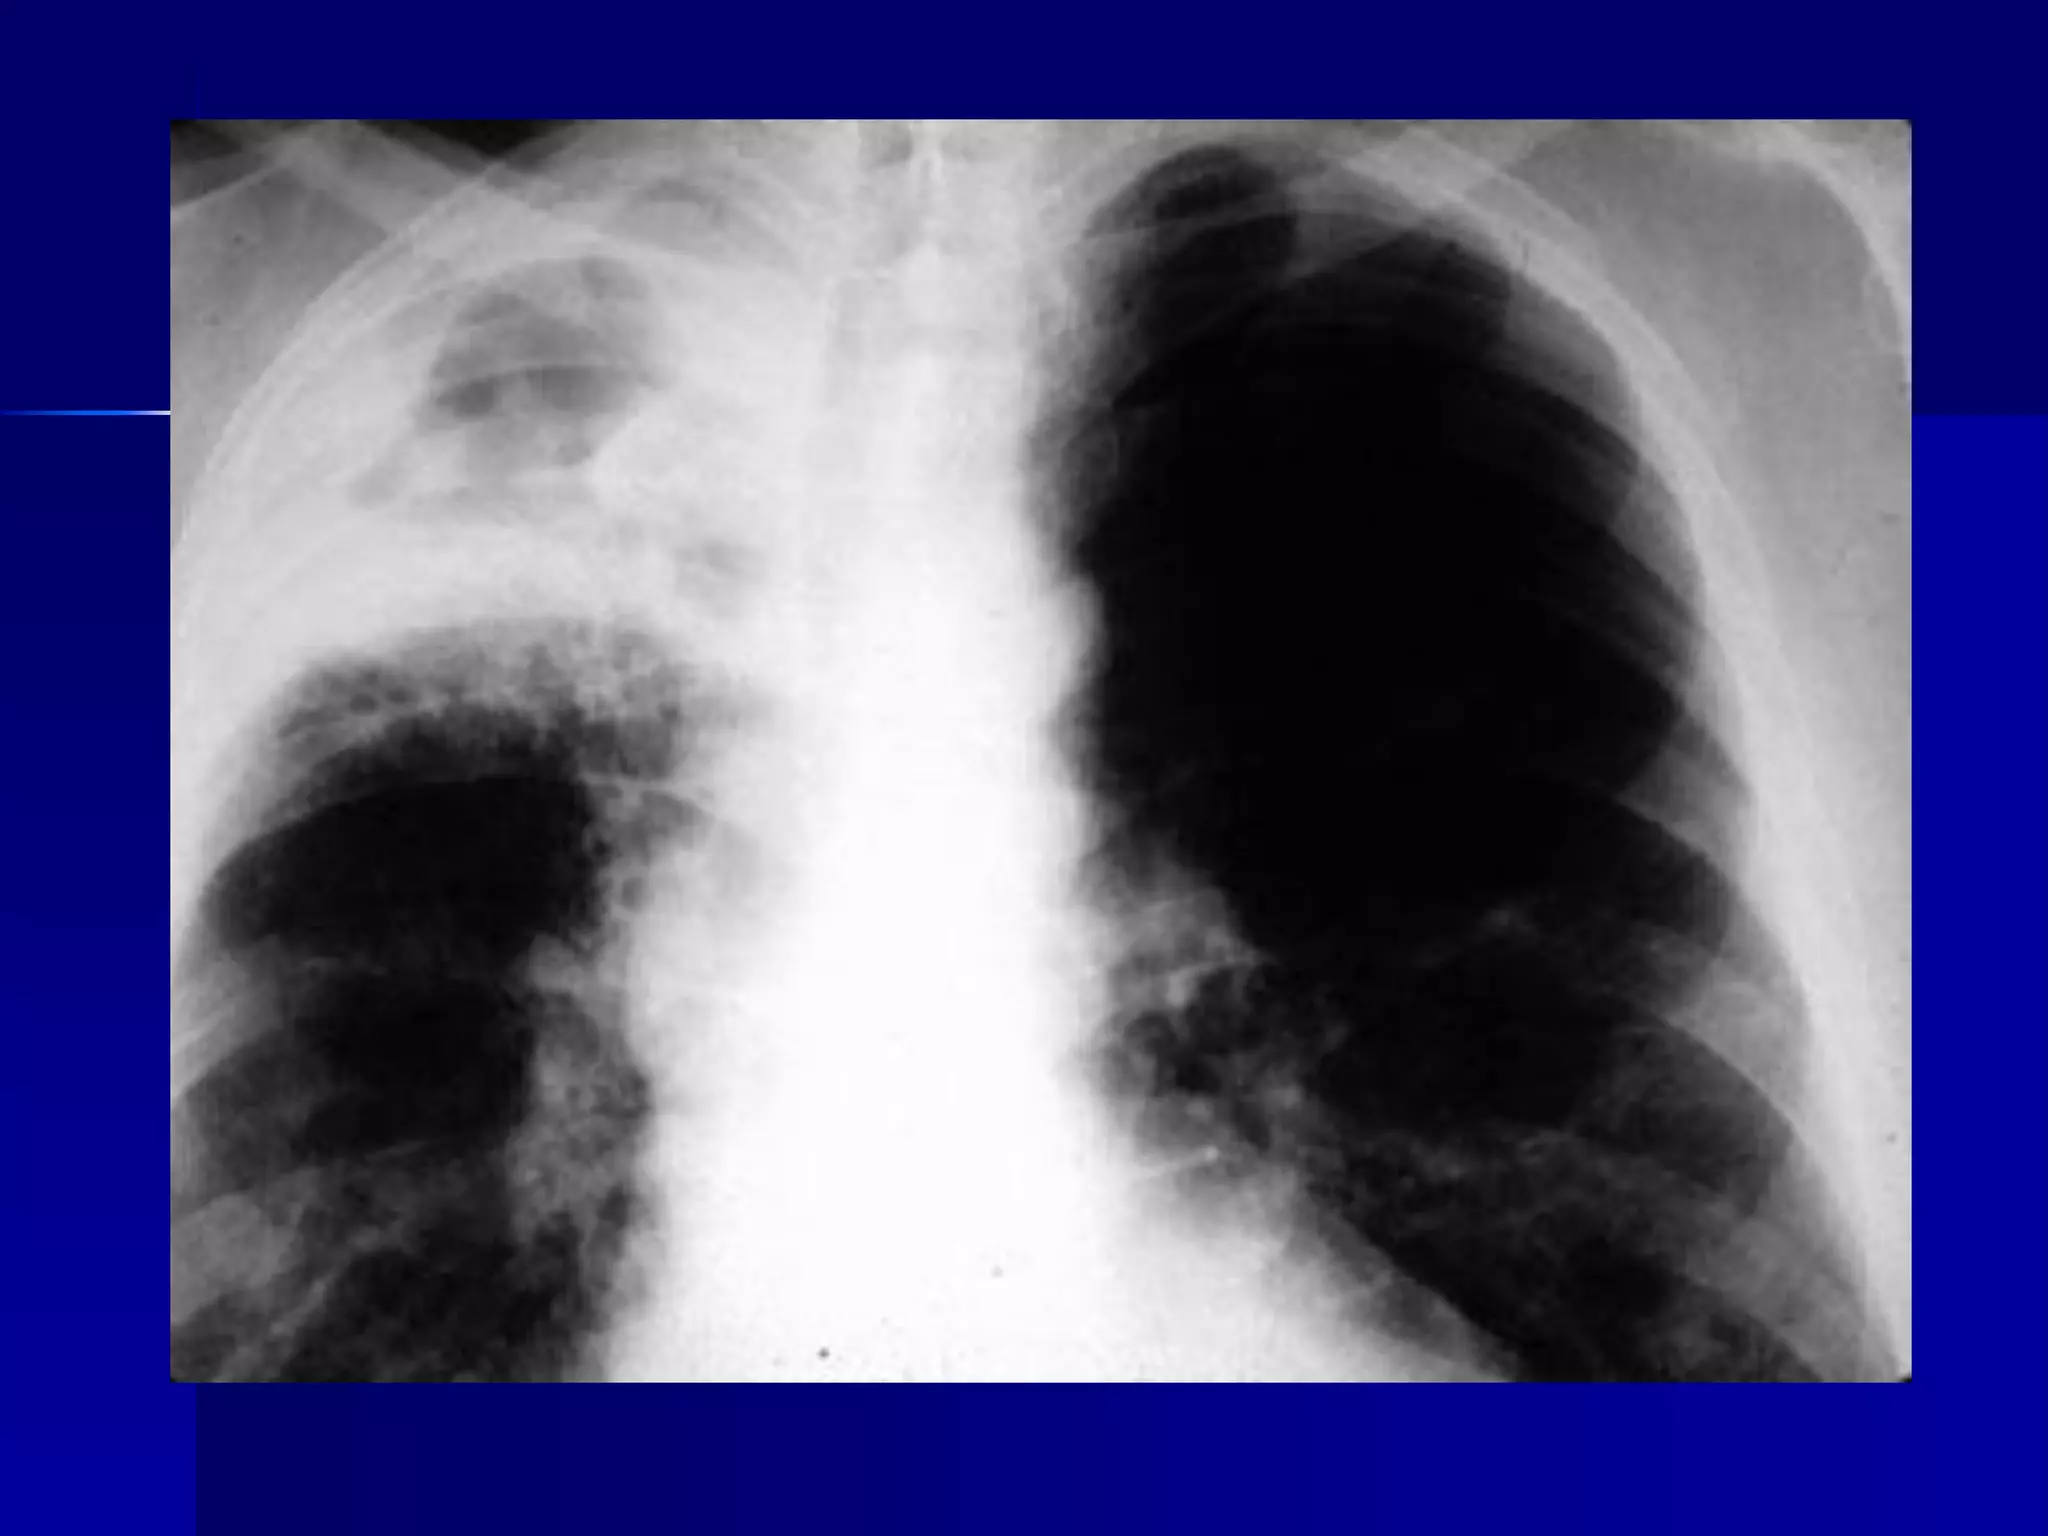

CXR Findings



Primary TB:

Reactivated TB:

Lower or middle lobe infiltrates

Apical infiltrates/cavitation

Latent TB:

Usually normal

 Nodules in hilar area or upper lobes

 Pleural scarring/thickening

Miliary Tuberculosis

Produced by acute dissemination of tubercle

bacilli via the blood stream.The term miliary

derives from the radiological picture of

diffuse, discrete nodular shadows about the

size of millet seed (2mm).

A- Classical form:

Radiology:

1. Bilateral upper zone fibrotic shadows: with

shift of trachea, mediastinum, distortion of

fissures and diaphragm, and elevation of the

pulmonary hila.

2. Soft confluent shadows of exudative lesion

(D.D pneumonia)

3 Calcification.

4. Cavitation.

5. Tuberculoma.

6. Hilar and paratracheal lymph node

enlargement may be present.